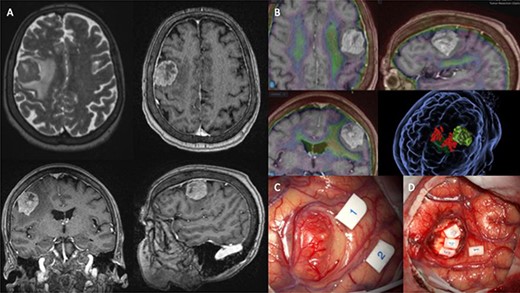

Presently, the patient underwent surgical resection utilising image guidance systems to provide accurate localisation of the tumour and minimise incisions when accessing the lesion. Part of this guidance imaging is shown in Fig. 1B. The surgical team also utilised intraoperative neuro-monitoring (IONM). Motor-evoked potentials (MEP) are shown in Fig. 1C and D. Unfortunately, the patient expired 16-weeks postoperatively.

(A) shows MRI sequences (top left) T2 axial, (top right) T1 post gadolinium axial, (bottom) T1 post-gadolinium coronal and sagittal. (B) 3D preoperative modelling and MRI-PET FDG Fusion. Light is tumour and dark green is cortico-spinal tracts. Red dots are positive motor responses – upper and lower limbs – during preoperative motor mapping with navigated transcranial magnetic stimulation. (C and D) show intraoperative microscope images of the tumour (C) and the post-resection tumour cavity (D). Tags 1 and 2 show the motor areas for tongue. At the depth of the tumour cavity (D), tag 3 also represents the motor area for the tongue, while tags 4 and 5 represent the Orbicularis Oris muscle.